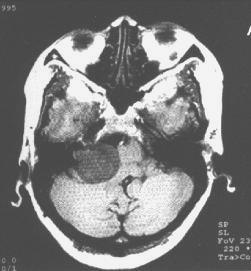

4.放射學檢查(1)顱骨X線片:岩骨平片見內耳道擴大、骨侵蝕或骨質吸收。(2)CT及MRI掃描:CT表現為瘤體呈等密度或低密度,少數呈高密度影像。腫瘤多為圓形或不規則形,位於內聽道口區,增強效應明顯。MRIT1加權像上呈略低或等信號,在T2加權像上呈高信號。第四腦室受壓變形,腦幹及小腦亦變形移位。注射造影劑後瘤實質部分明顯均一強化,囊變區不強化。

(3)CT及MRI檢查:目前聽神經鞘瘤診斷的標準是Gd-DTDA增強的MRI,特別是當腫瘤很小(<1cm)或在內聽道內,CT掃描陰性又高度懷疑腫瘤存在時應該進行GD-DTPA增強的MRI。CT與MRI兩種檢查有相輔相成的作用,如CT發現有病側內聽道擴大時,增強CT可發現腫瘤對於估計中顱窩入路時顳骨的氣化程度及高頸靜脈球與後半規管及底的距離有幫助。如果病人已作了CT而腫瘤較大,MRI可提供對腦幹壓迫的範圍Ⅳ腦室是否通暢腦積水、是否存在的情況對可疑聽神經鞘瘤或CT檢查難於確定時,全序列的MRI可做出鑑別診斷。但也要注意Gd-DTPA的可能假陽性,這與內聽道內神經的炎症或蛛網膜炎有關;任何小的接近底部的增強病變應該在六月後作MRI複查,以評估其生長情況。